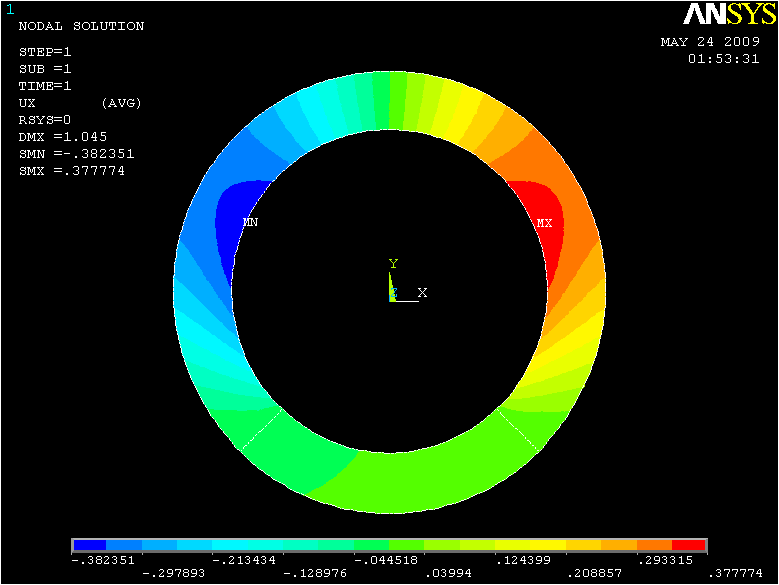

In case of plane strain, the problem at hand can be simplified as follows. Assume that we have an inhomogeneous ring cylinder with a known height. Since the foundation of our research is based on the assumption of plain strain/stress, there is no strain/stress along the direction and therefore the cylinder’s height doesn’t have any effect on the solution. The assumption of an inhomogeneous ring cylinder is because of the changes occurred in the mechanical properties of heart muscle after introducing infarction. After defining the elastic properties of the ring cylinder, the structure is ready for the next step which is loading. In this step the load is applied in a uniform and radial manner inside the ring, to mimic the process of loading the heart muscle. The internal pressure applied to the ring is time varying. Fig.3 represents the results of ANSYS analysis of the ring for displacement in , and the absolute values of displacements respectively.